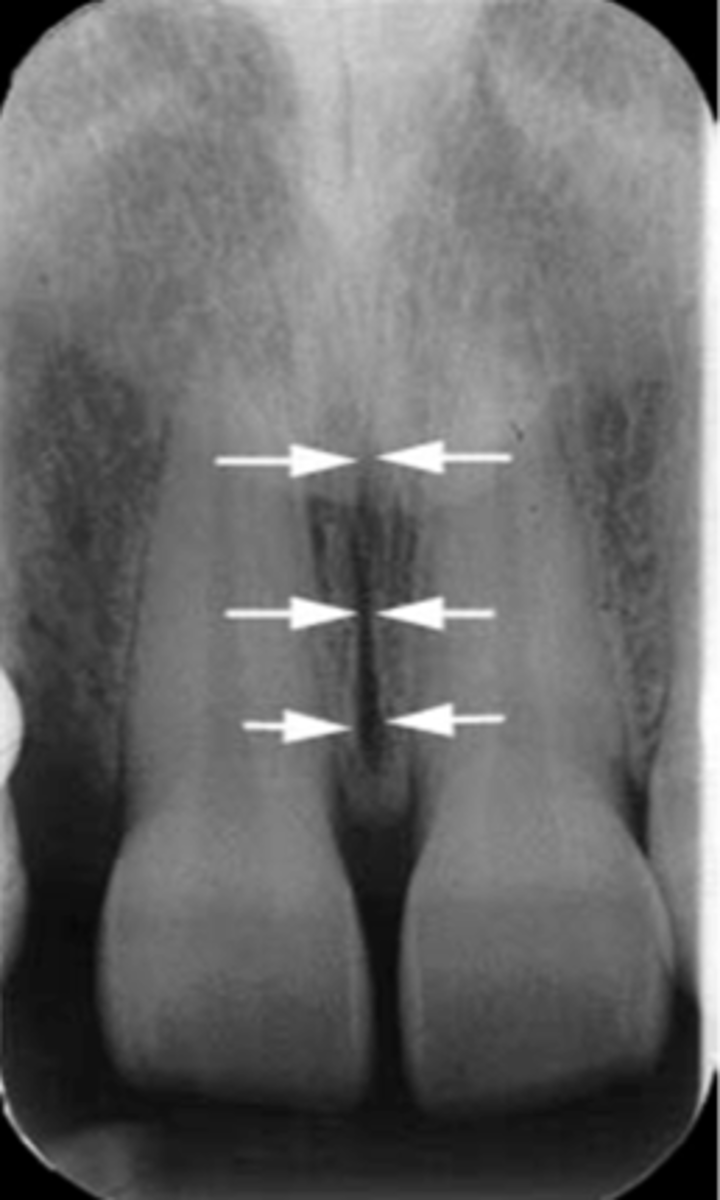

Nasopalatine duct

What is the wide, vertical structure indicated by the arrows?

<p>What is the wide, vertical structure indicated by the arrows?</p>

Nasopalatine canal

Identify the structure

<p>Identify the structure</p>